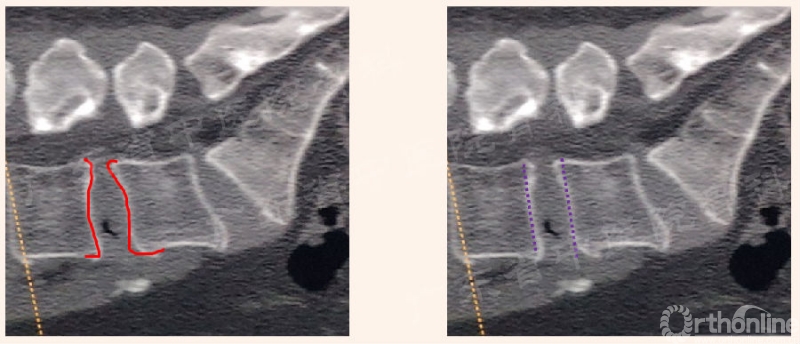

进入椎管的相关操作

黄韧带的处理